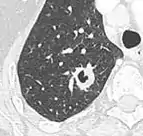

- If there is a central cavity, then a thin wall points to a benign cause whereas a thick wall is associated with malignancy (especially 4 mm or less versus 16 mm or more).[10]

Cavitation with relatively thick wall, in this case aspergilloma).[9]